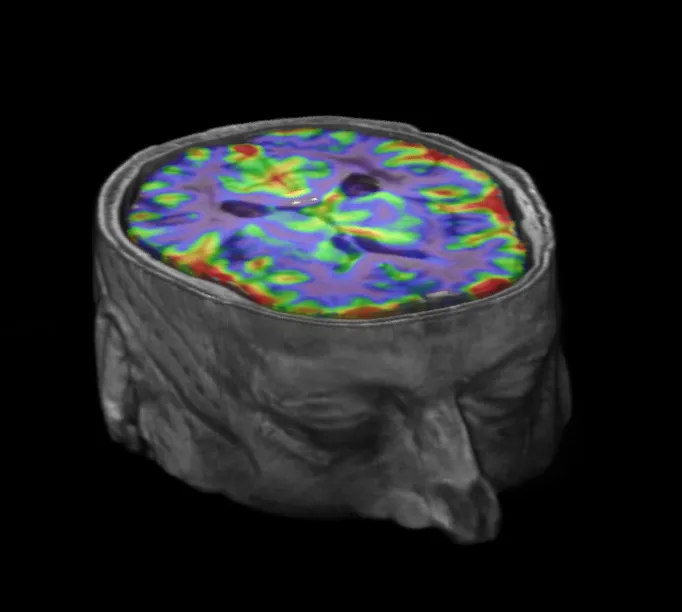

The INVESTIGATE@SVDs study, a collaborative study apart of the larger SVDs@TARGET project, has come to an end. About the study Image Cerebrovascular reactivity (CVR) map overlaid on T1-w image. INVESTIGATE@SVDs is the first multi-centre study to combine complex imaging protocols which allowed the team to assess: Blood brain barrier (BBB) function & dysfunction, in small vessel diseases (SVDs) & Cerebrovascular reactivity & pulsatility in small vessel diseases (SVDs) This provided a holistic brain vascular health assessment & the acquired data will help the team understand the complex relationship between blood-pressure & microvascular defects associated with small vessel diseases (SVDs). This study is part of the larger SVDs@Target project, which seeks to identify the key mechanisms behind small vessel diseases (SVDs) in stroke & dementia. This larger SVDs@Target project is a collaborative effort between hospitals in: Edinburgh Oxford Munich Maastricht Utrecht Outcomes The data analysis is at an early stage but the team are already seeing that blood vessels are less able to increase blow flow to the brain when needed in patients with lots of vascular damage, whereas simply having higher blood pressure measures was not enough to explain vascular damage. The various techniques to image how well blood vessels are working in the brain will allow the team to unpick the processes driving damage in more detail. We asked Dr Gordon Blair his thoughts regarding the INVESTIGATE@SVD’s study coming to an end: “The complexity of the brain scans used in INVESTIGATE has previously limited their use to small studies in one place at a time, making them less useful for developing new treatments. Image FLAIR scan with BBB permeability & CVR maps. Successfully completing INVESTIGATE using so many measures of brain blood vessel health, across three countries is therefore a huge achievement & a reflection of the hard work & lengthy efforts of a substantial number of researchers. We’re extremely grateful to all our study participants who gave their time to help better understand what causes blood vessels to become damaged in the lead up to strokes & vascular dementia. The techniques developed in INVESTIGATE are now being used in clinical trials trying to identify new treatments.” - Dr Gordon Blair, lead INVESTIGATE research fellow Early results for the INVESTIGATE@SVD’s study will be presented at the European Stroke Organisation / World Stroke Organisation virtual conference in November. Related links Professor Joanna Wardlaw Dr Gordon Blair Dr Fergus Doubal Dr Michael Thrippleton Dr Michael Stringer ESO-WSO Virtual Conference Brain & nervous system Small vessel disease (SVD) Stroke Dementia INVESTIGATE@SVDs SVDs@TARGET 27 Mar 20. INVESTIGATE@SVDs Milestone 23 Apr 19. Investigate@SVDs final volunteer 05 Jul 17. Investigate@SVDs starts Social media tags & titles The INVESTIGATE@SVDs study, a collaborative study apart of the larger SVDs@TARGET project, has come to an end. @SVDs_at_target @EdinUniBrainSci @fergusdoubal #SmallVesselDisease Publication date 07 Oct, 2020